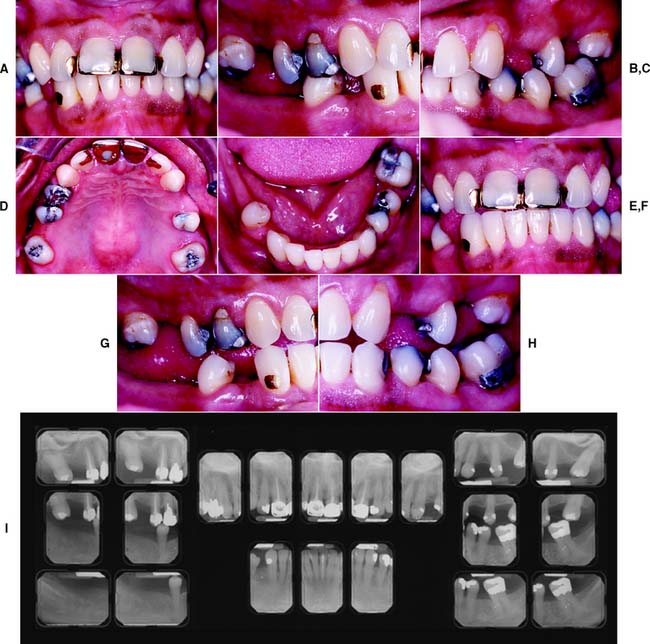

This class (Figs. 1-33 and 1-34) is characterized by severely compromised location and extent of edentulous areas with guarded prognosis, abutments requiring extensive therapy, occlusion characteristics necessitating reestablishment of the occlusion with a change in the occlusal vertical dimension, and residual ridge conditions.

Fig. 1-33 Class IV patient. Edentulous areas are found in both arches, and the physiologic abutment support is compromised. Abutment condition is severely compromised as a result of advanced attrition and failing restorations, necessitating extracoronal restorations and adjunctive therapy. The occlusion is severely compromised, necessitating reestablishment of occlusal vertical dimension and proper occlusal scheme. A, Frontal view, maximum intercuspation. B, Right lateral view, maximum intercuspation. C, Left lateral view, maximum intercuspation. D, Occlusal view, maxillary arch. E, Occlusal view, mandibular arch. F, Frontal view, protrusive relationship. G, Right lateral view, right working movement. H, Left lateral view, left working movement. I, Full-mouth radiographic series.

(From McGarry TJ, et al: Classification system for partial edentulism. J Prosthodont 11:181, 2002.)

Fig. 1-34 Class IV patient. The patient is categorized as Class IV because advanced attrition of the occlusal surfaces is present in more than three sextants. The occlusion is severely compromised with the need to reestablish occlusal vertical dimension and a proper occlusal scheme. A, Frontal view, maximum intercuspation. B, Right lateral view, maximum intercuspation. C, Left lateral view, maximum intercuspation. D, Occlusal view, maxillary arch. E, Occlusal view, mandibular arch. F, Panoramic radiograph.

(From McGarry TJ, et al: Classification system for the completely dentate patient. J Prosthodont 13:73, 2004.)

Other characteristics include severe manifestations of local or systemic disease, including sequelae from oncologic treatment, maxillomandibular dyskinesia and/or ataxia, and refractoriness (a patient’s presenting with chronic complaints after appropriate therapy).